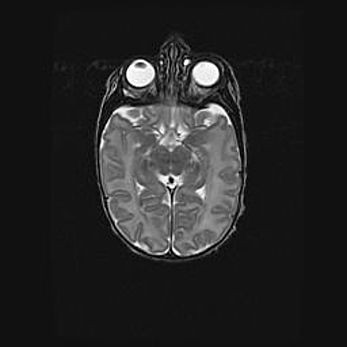

Множественные кисты обоих полушарий головного мозга, наибольшая из них в правой затылочной области. Ассиметричная атрофическая гидроцефалия.

Возраст: 7 месяцев

Вес: 5660 г

Пол: мужской

Окружность головы: 41,5 см

Срок гестации: 28-29 недель

Кисты головного мозга развиваются в результате многоочаговых некрозов вещества мозга и возникают вследствие перенесенной перинатальной инфекции, менингитов, энцефалитов, асфиксии, родовой травмы, расстройств мозгового кровообращения различного генеза. Образованию кист в веществе головного мозга плодов и новорожденных способствуют такие факторы, как высокое содержание в нем воды, недостаточная (или отсутствие) миелинизация и слабая астроглиальная реакция на повреждение.

Кисты могут сочетаться с гидроцефалией и другими поражениями головного мозга.